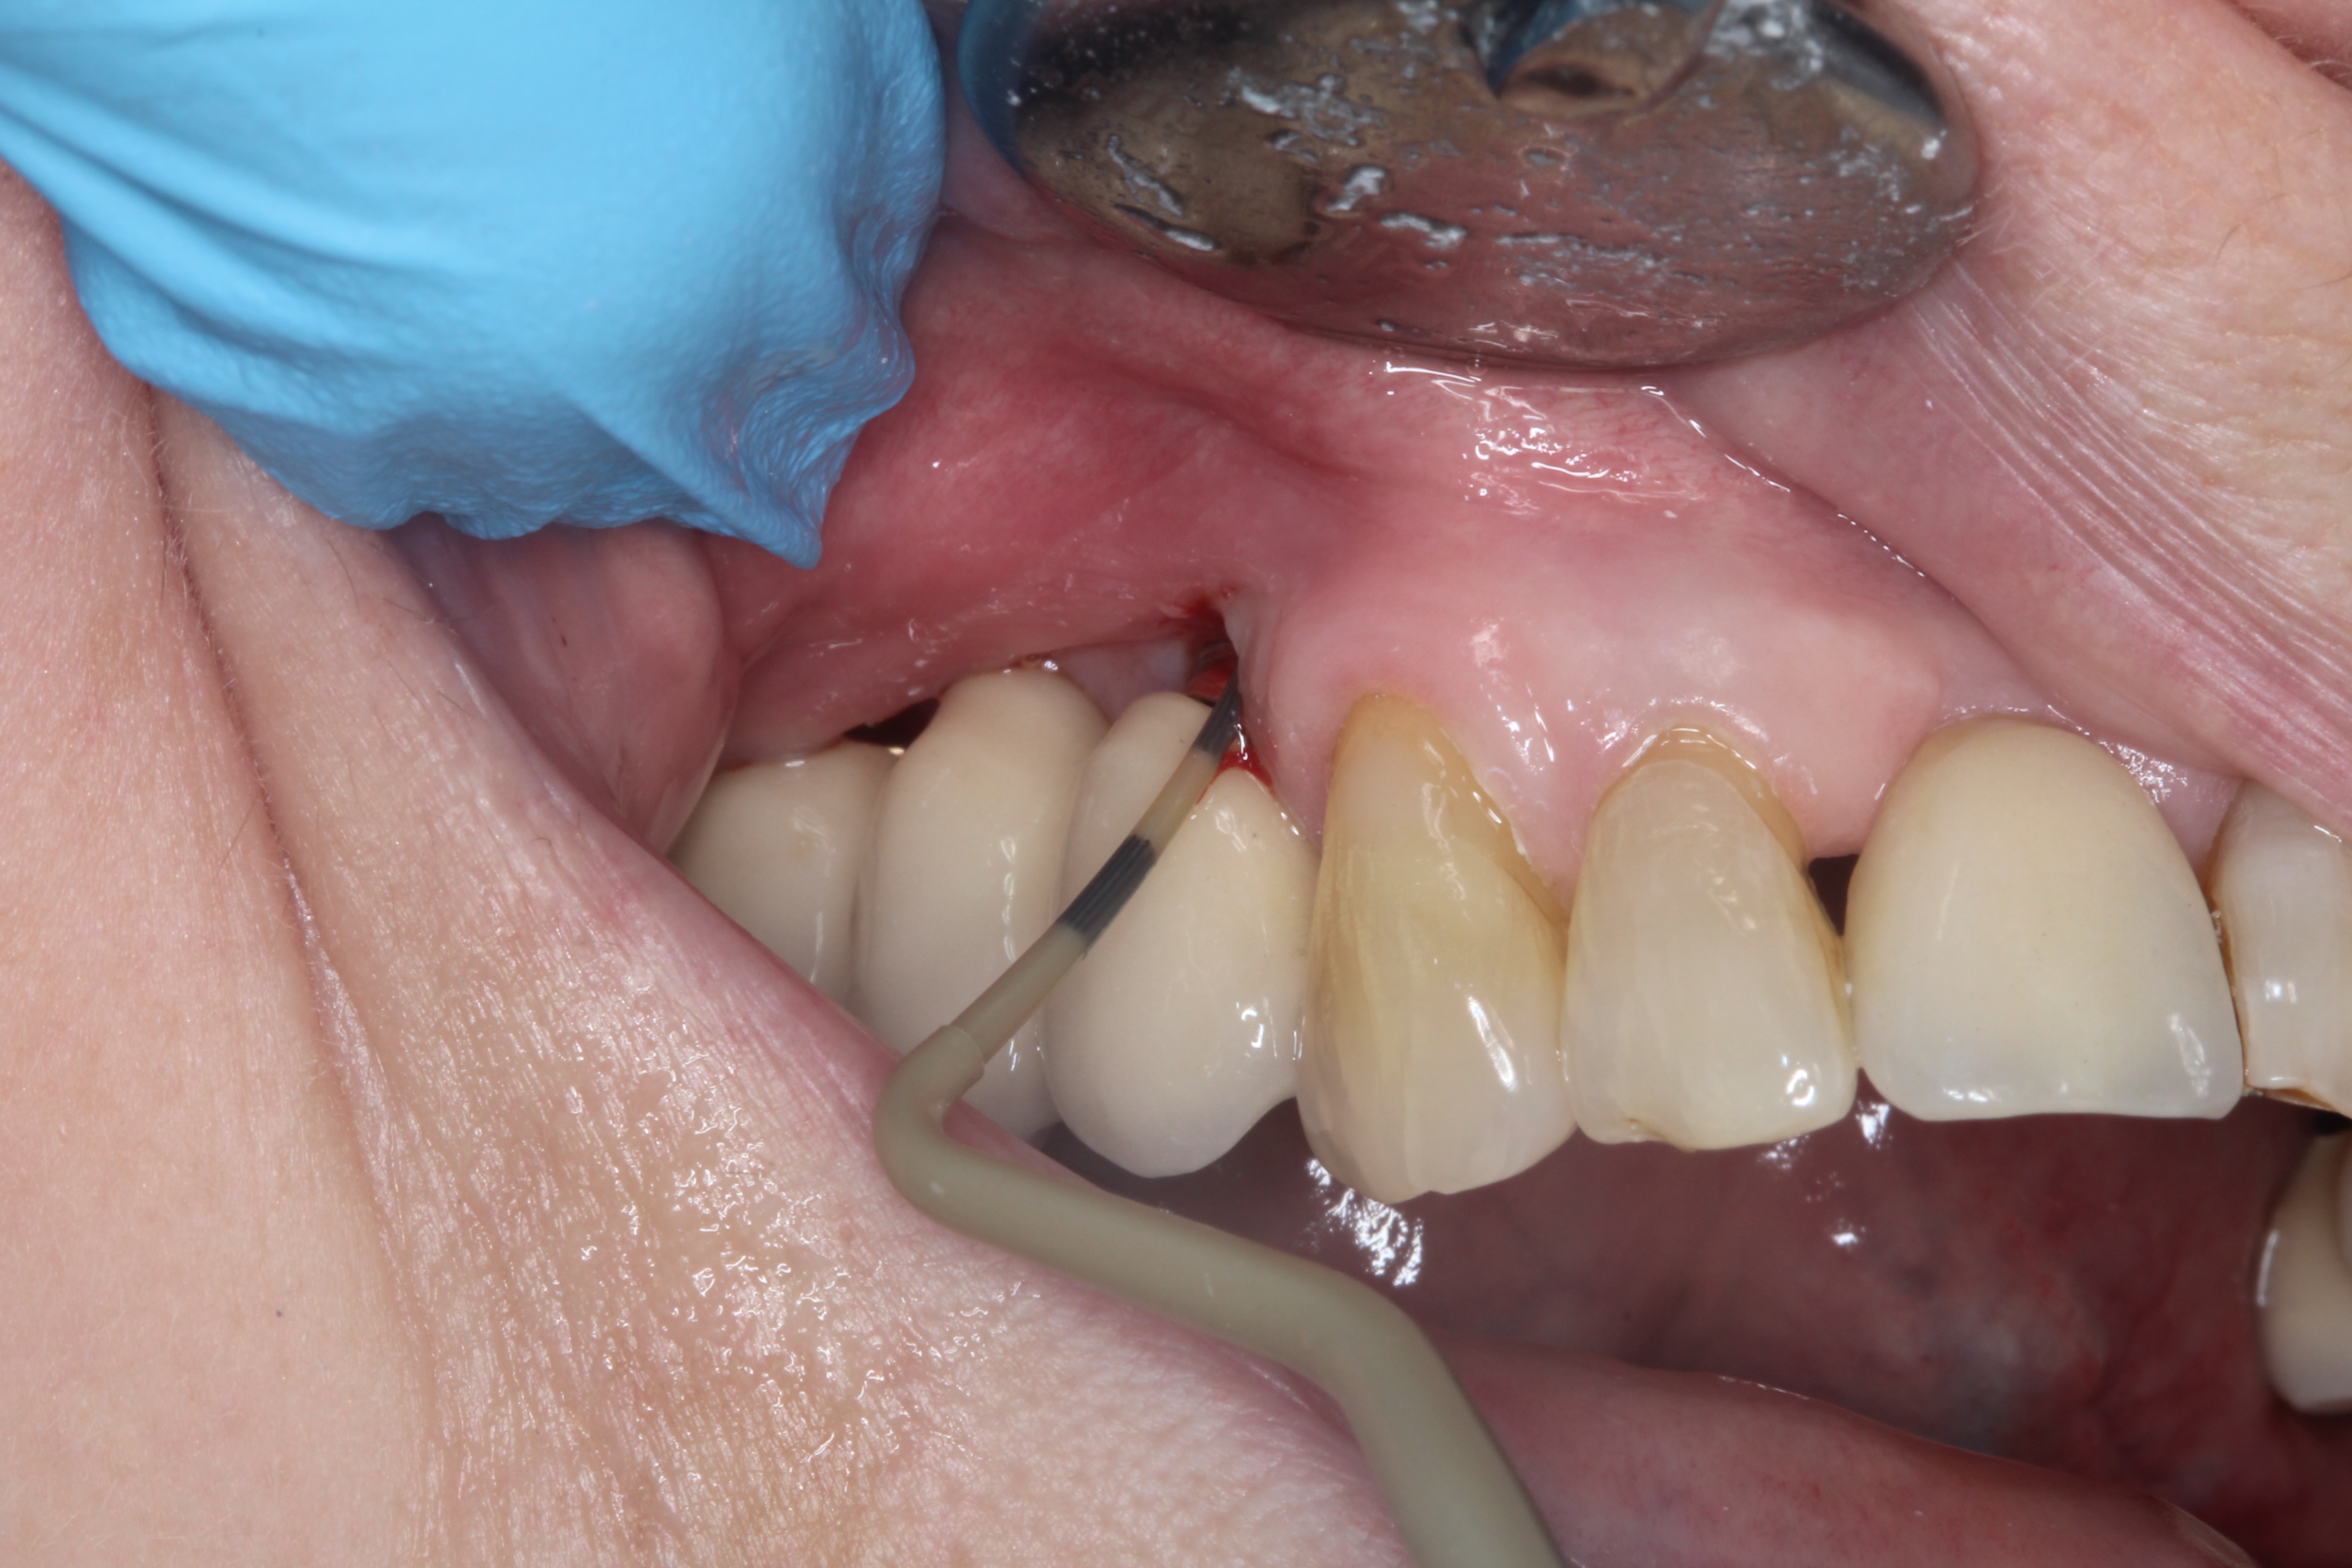

The key steps to probing during a dental implant health assessment Dentistry.co.uk Periodontal Probing Around Implants if probing around implants is not part of the periodontal protocol at your office, it is imperative that three out of the five methods for evaluating. the clinical implant should be examined to evaluate the following: Condition of the soft tissues, plaque index, clinical probing depth, bleeding on. quirynen et al 23 concluded that, in the presence. Periodontal Probing Around Implants.

Periodontal Probing Around Implants . if probing around implants is not part of the periodontal protocol at your office, it is imperative that three out of the five methods for evaluating. Condition of the soft tissues, plaque index, clinical probing depth, bleeding on. The mpli, modified bleeding index (mbli), calculus score, ppd, and recession decreased from 1 month to 12 months in. quirynen et al 23 concluded that, in the presence of moderately healthy periimplant soft tissues, the use of a periodontal probe. the clinical implant should be examined to evaluate the following: